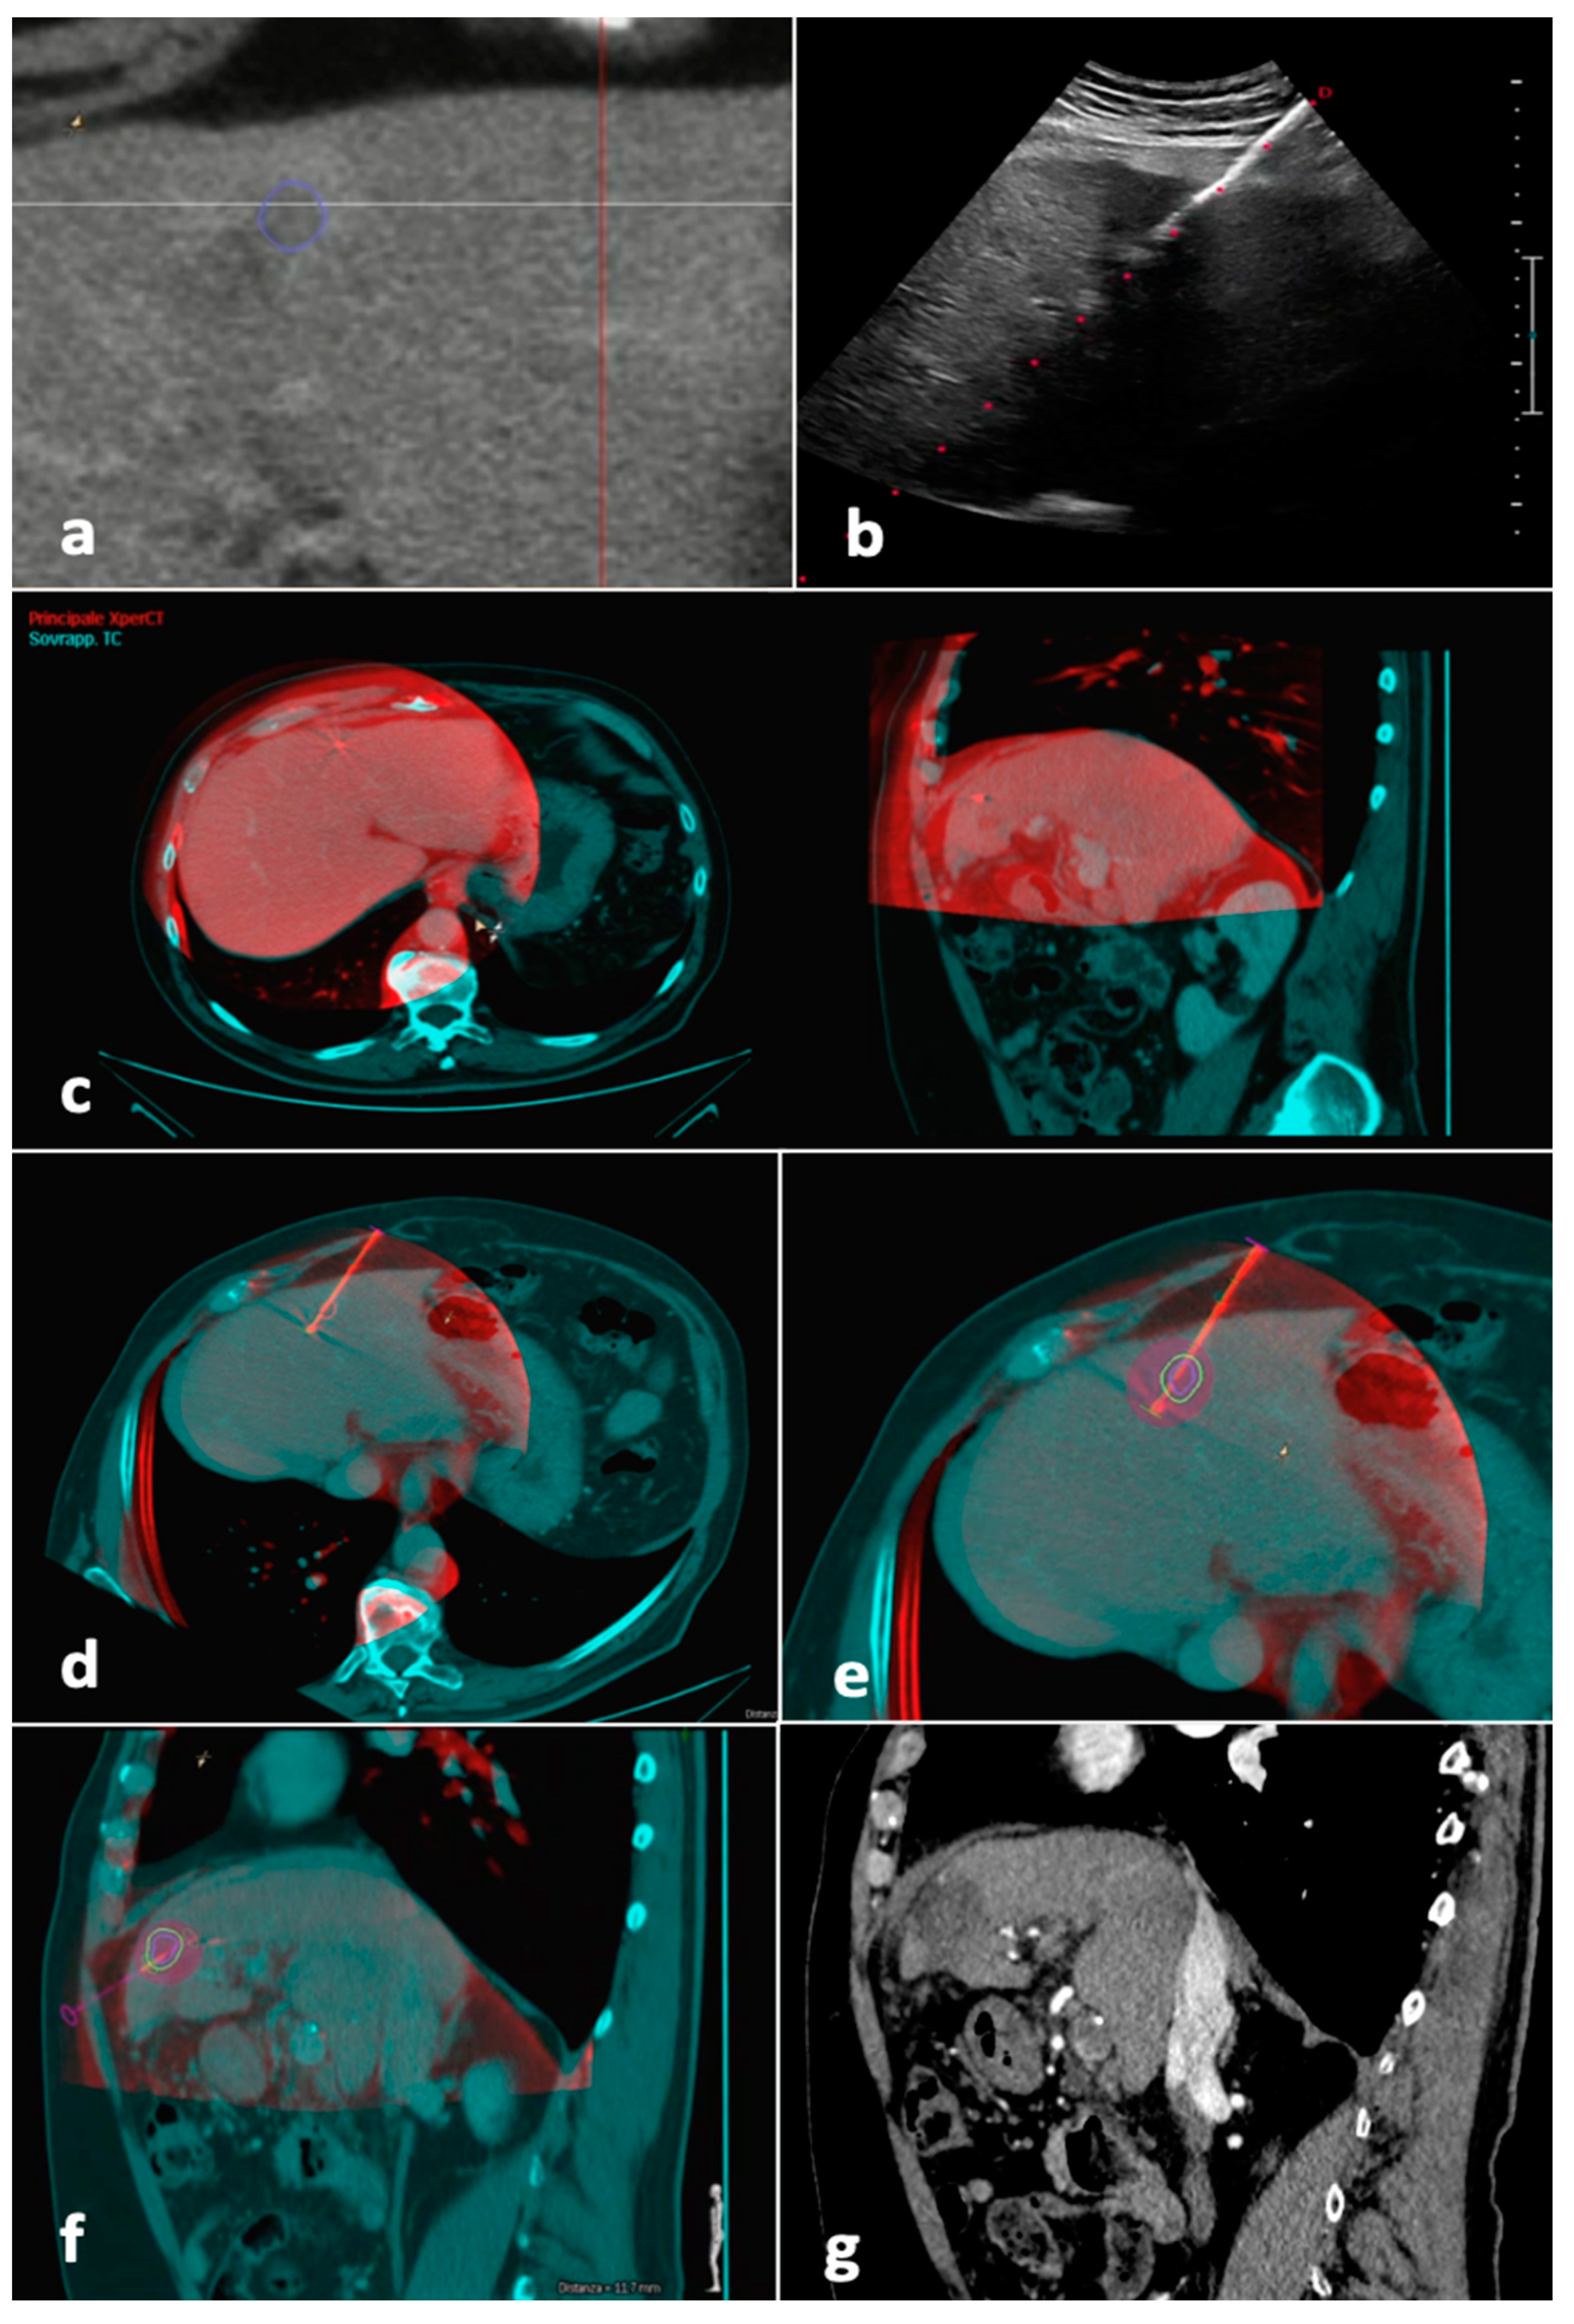

The protocol’s steps used to treat Group A patients are represented in Figure 2. First, pre-procedural CT/MR images were loaded to a workstation (XtraVision, Philips Image-Guided Therapy) and the tumor was segmented.

After having been transferred to the workstation, the unenhanced CBCT images, showing the antenna position, were registered to the pre-procedural CT/MR images, showing the tumor. Software (Allura Xper FD20 Philips Medical Systems, Netherlands), was then used to place a “virtual antenna” exactly over the real one, at the tip of which, after having selected the desired ablation power and time, the predicted ablation volume was displayed. The aim was coverage of the tumor with a 5 mm safety margin, avoiding non-target structures (Figure 3).

If the antenna resulted in a suboptimal position, this was changed under US guidance and another CBCT was performed; this step was repeated until a satisfactory result was obtained. Ablation was performed under US surveillance. Immediate post-procedural US and/or unenhanced CBCT was performed in order to detect early complications. [21]

Figure 3. Tumor segmentation, fusion imaging and ablation volume prediction. The tumor, located in the left liver lobe, was semi-automatically segmented (blue line) before the procedure on CT images (a). The microwave antenna was positioned into the tumor with US guidance (b). When the operator judged the antenna to be in place, CBCT was performed with the patient possibly holding their breath. Manual fusion between pre-procedural CT images showing the tumor (blue) and intraprocedural unenhanced CBCT images demonstrating the microwave antenna (red) was performed, with fused images showing axial and sagittal planes (c). On the fused images, a “virtual antenna” was positioned over the microwave antenna (d). The predicted ablation volume was generated based on ablation time and power selected (purple), which in this case, completely covers the target tumor (blue line) and the 5 mm safety margin (green line) in the axial (e) and sagittal (f) planes. (g) Follow-up sagittal image in the arterial phase obtained 1 month after procedure shows complete response. Abbreviations—CBCT, cone-beam CT; US, ultrasound.